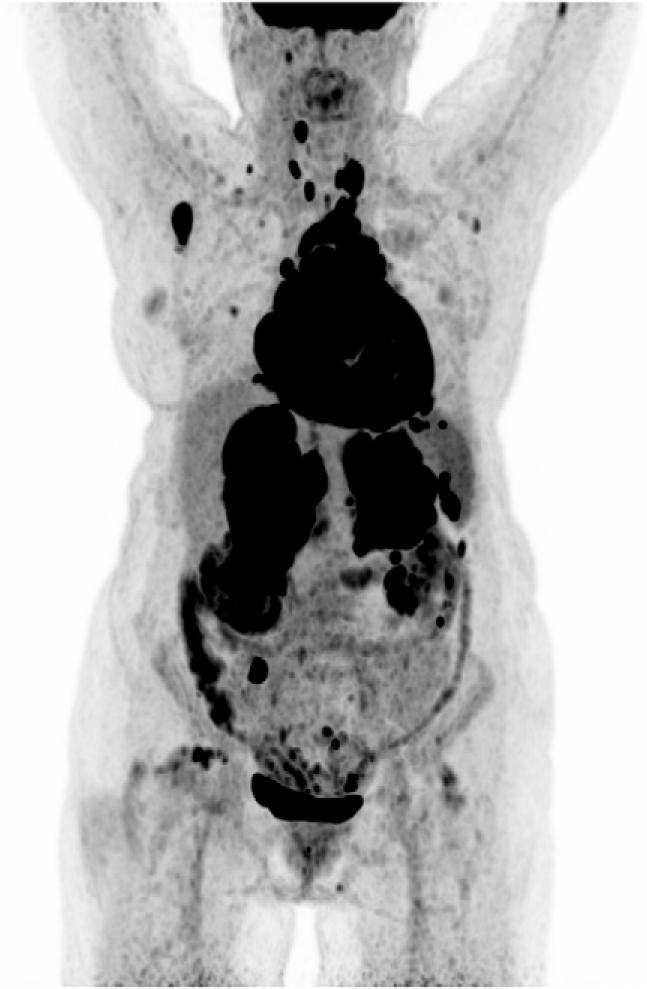

The patient was discharged home in good condition. Two weeks later, at the end of April 2024, a [18F]FDG PET/CT scan was performed to further evaluate the lesions visualized on HRCT.

[18F]FDG PET/CT, Maximum Intensity Projection (MIP) image – shows disseminated areas of increased radiotracer uptake in the whole body, including the adrenals, liver, spleen, intestines, bones, thyroid, heart, and multiple lymph nodes.

Additionally, proliferative foci were visualized in the liver, spleen, kidneys, bones, peritoneum, upper abdominal and thoracic lymph nodes, and bilaterally in the pleura. Also, metabolically active nodules in the thyroid gland were observed. Intestinal involvement was inconclusive, with thickening of the cecal wall and a single focus in the sigmoid colon. Given the advanced extent of metastatic disease, it was not possible to identify the primary site. The overall imaging pattern raised suspicion for a lymphoproliferative process and warranted its inclusion in the differential diagnosis.